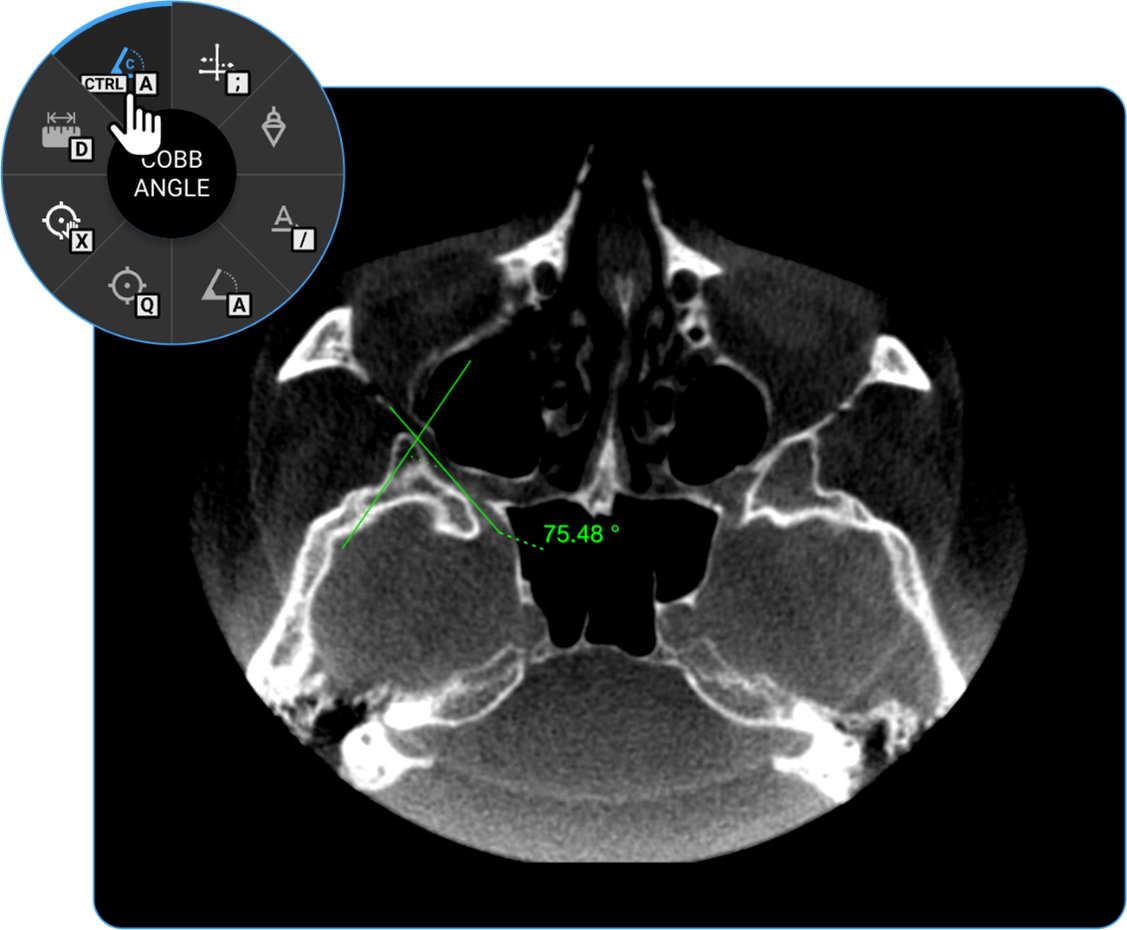

1. Cobb Angle: Locate the Cobb Angle tool on the adjustment wheel and click on it to measure the degree of spinal curvature, aiding in scoliosis assessment.

vai

1. Angle: Click on the Angle tool to determine the angle between two intersecting lines, assisting in anatomical evaluations.